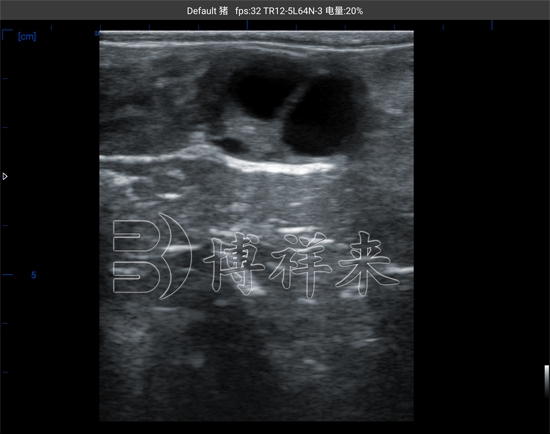

在规范操作条件下,牛用B超机能够清晰显示子宫内的超声特征变化。随着妊娠进程推进,子宫腔内的回声结构会发生规律性的变化,这些变化是判断妊娠状态的重要依据。

与经验判断不同,B超检测并不是凭感觉“看像不像”,而是结合图像特征,对子宫内容物进行客观判断。这也是为什么在现代奶牛场中,超声检测逐渐取代单一经验判断,成为妊娠确认的重要手段。